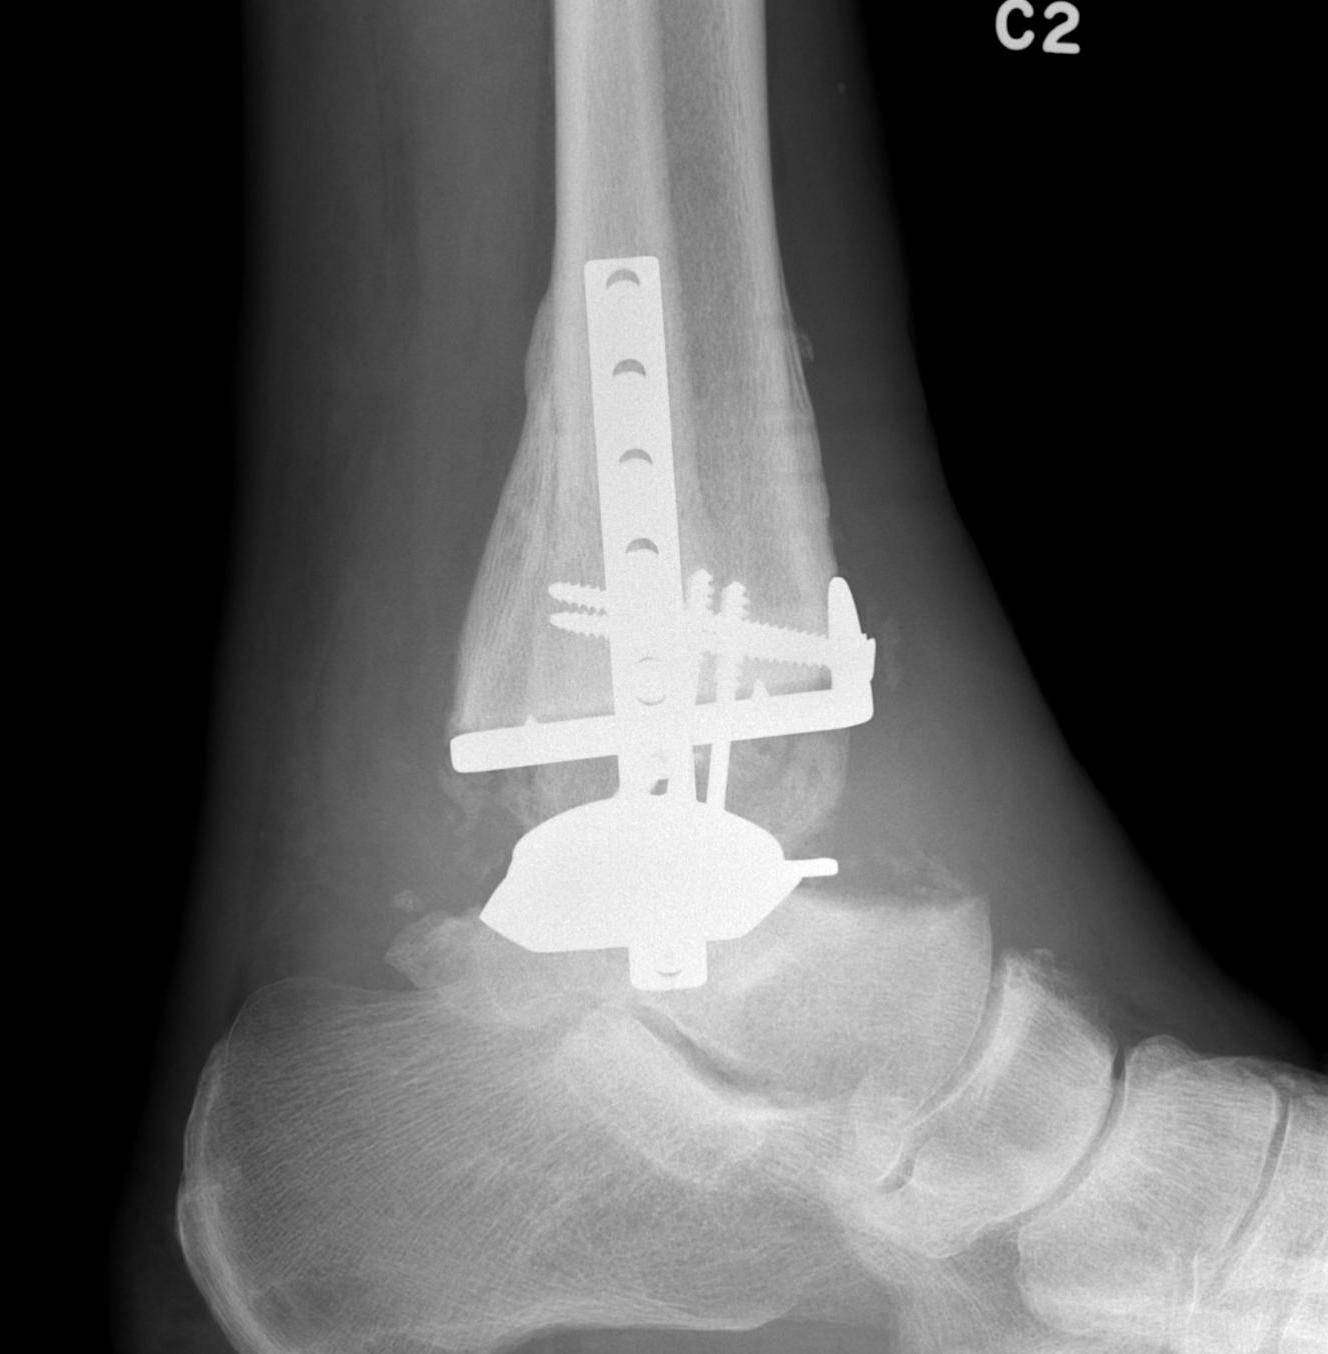

A. Anterior approach

Smith & Nephew Salto Tolaris Technique PDF

Vumedi total ankle arthroplasty via anterior approach

Vumedi total ankle arthroplasty with patient specific jigs

Protect SPN and divide extensor retinaculum

- between Tibialis anterior and EHL

- retract neurovascular bundle laterally

- remove anterior osteophytes

Tibial cut

- distal alignment jig / extramedullar jig +/- image intensifier +/- patient specific jigs

- resect few mm above eroded bone

- preserve medial and lateral malleolus

Talar dome resurfacing

- jig to make chamfer cuts

Insert mobile / fixed bearing